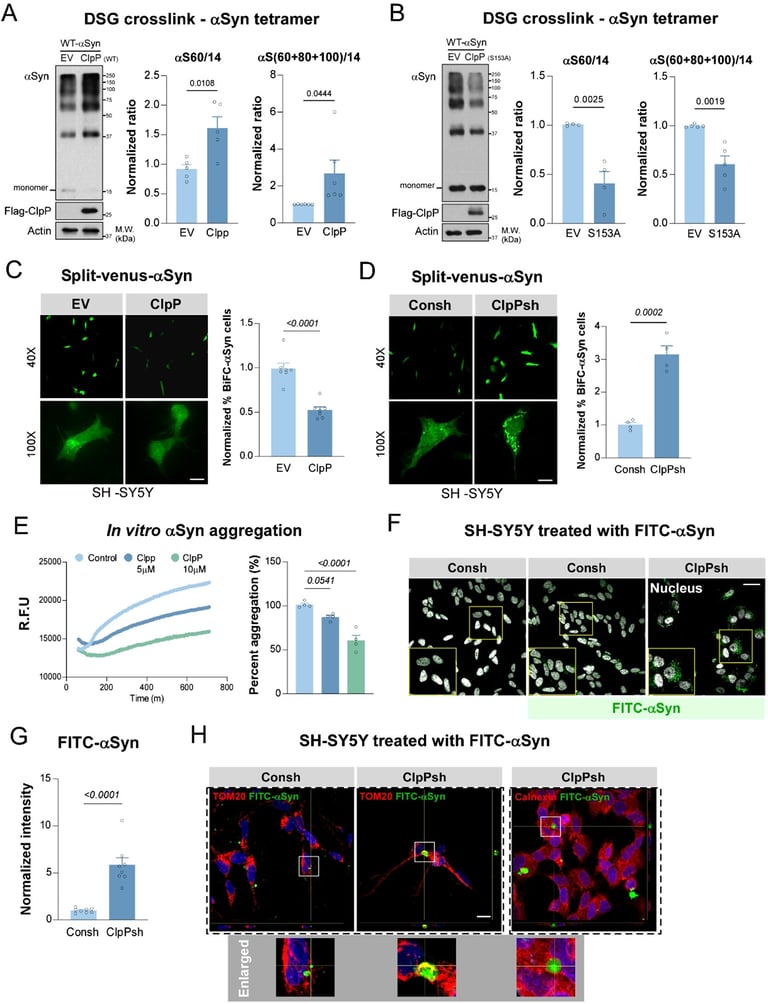

Case Western Reserve University researchers identify a harmful interaction between alpha-synuclein and the mitochondrial protein ClpP that impairs mitochondria and accelerates neuron death in Parkinson’s disease.

A designed treatment named CS2 acts as a decoy that lures alpha-synuclein away from the mitochondrial enzyme ClpP, restoring mitochondrial function and reducing brain inflammation across human brain tissue, patient-derived neurons, and mouse models.

Lead author Di Hu and colleagues emphasize that this approach targets a root cause of Parkinson’s disease rather than merely addressing symptoms.